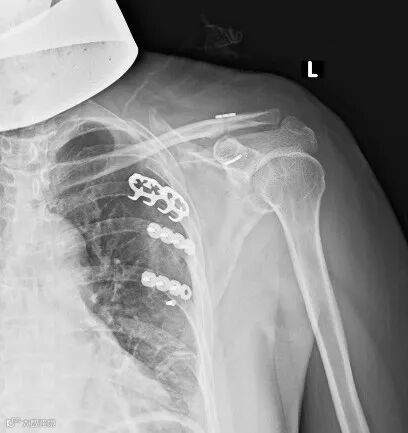

(传统手术,创口大)

带袢钢板微创内固定术

术后(伤口小)

带袢钢板是在锁骨和喙突间再一次建立了喙锁韧带相似的解剖构造(相当于为患者重建一条“韧带”),在纵、横向两个方向都起到了坚强的稳定作用,且重建的结构大于喙锁韧带的强度,具备较好的稳定性及疗效。

所以此种手术方式,有手术时间短、术中出血少、创伤小、住院时间短及费用少、术后肩关节功能良好等优点,较锁骨钩钢板而言具有一定优势。